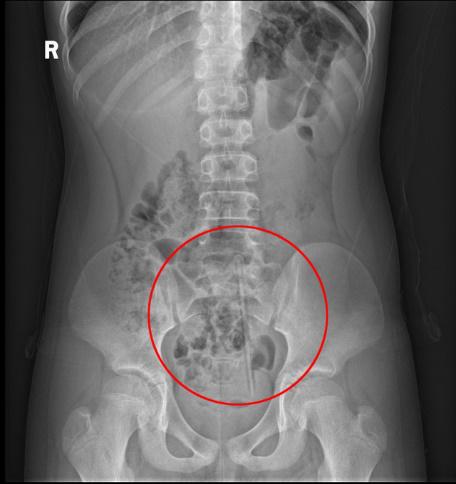

男孩称此举是想模仿《荒野求生》里的贝爷将海水灌入肛门吸收水分,看看龙虾能不能变成龙虾干……更离谱的是,男孩塞入的龙虾是活的,龙虾顺着直肠挣扎,钳子严重划伤男孩肠道,并且龙虾越爬越深,导致男孩腹痛难忍。医生通过手术才将龙虾从其直肠中取出。

还有一个出来难的地方就是直肠,肛门有内外两层括约肌把守,外括约肌是与外界连通的“大门”,控制你在不该排便的场合守住最后防线;内括约肌平常呈收缩状态,当直肠充满粪便时张开协助排便,当收到刺激后会产生痉挛,自动收缩。所以向肛门塞入异物,想拿出来的时候由于紧张和异物刺激,还会越塞越紧。